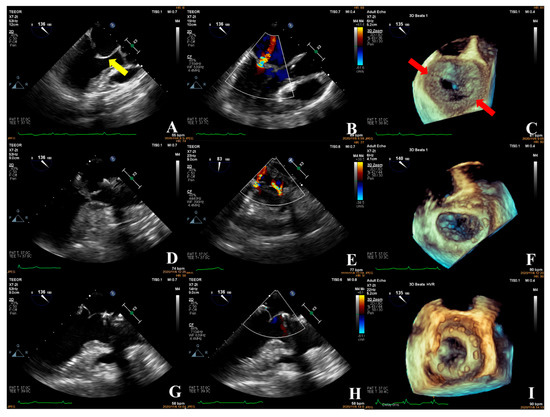

- In the simple group, the etiology was primarily secondary annular enlargement or mitral valve prolapse in an isolated segment leading to mitral regurgitation. The most commonly used technique was annuloplasty. The coaptation area of the valve leaflets was increased to reduce or even eliminate mitral regurgitation. For example, the complexity score was 3 (2 + 1) for a patient with A1 segment prolapses, a mitral anterior leaflet cleft, no chordae tendineae rupture, and no leaflet calcification, which classified the patient in the simple group. The cleft was sutured during the operation and a mitral annuloplasty ring was placed. The surgical technique score was 2 (1 + 1). After resuscitation, the surgical effect was good and no obvious regurgitation signal was observed (Figure 7).